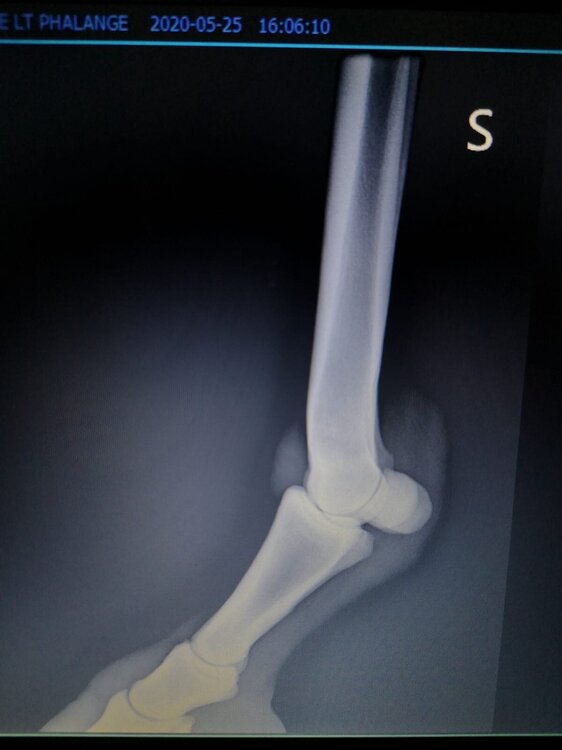

Salve volevo chiedervi qualche informazione in merce tò a un problema che ho avuto con la mia puledra. Qualche settimana fa mentre stavo lavorando alla corda è scivolata urtato l'arto posteriore sinistro. Arrivati in box ho messo dell'acqua a pressione perché si era gonfiato sia il nodello sia il pastorale. Già l'indomani l'arto era sgonfio ritornato normale, quindi ho continuato a lavorarla. Ma dopo qualche giorno di lavoro alla corda leggerissimo, al rientro in box ho notato che sia il nodello che il posturale gonfiavano nuovamente. Allora ho chiamato il veterinario che ha detto che la cavalla aveva una lussazione e mi ha insegnato come cura una fasciatura con della creta per 24h per cinque giorni e un antinfiammatorio. Dopo un paio di giorni la fasciatura ha fatto come delle vesciche e il gonfiore è aumentato dal pastorale alla garra. Abbiamo chiamato un altro veterinario abbiamo fatto vedere anche a lui la cavalla e diceva che poteva essere la frattura del ditino, ma si dovevano fare le lastre per essere sicuri. Ora abbiamo fatto le lastre e il radiologo dice che c'è dell'infiammazione ma non c'è niente di grave. Il veterinario,viste le lastre dice che deve essere operata. Allora abbiamo consultato un'altro veterinario che dice che la cavalla non ha assolutamente niente. Ora io vi allego le radiografie, datemi un vostro parere perché non só più cosa fare. Grazie